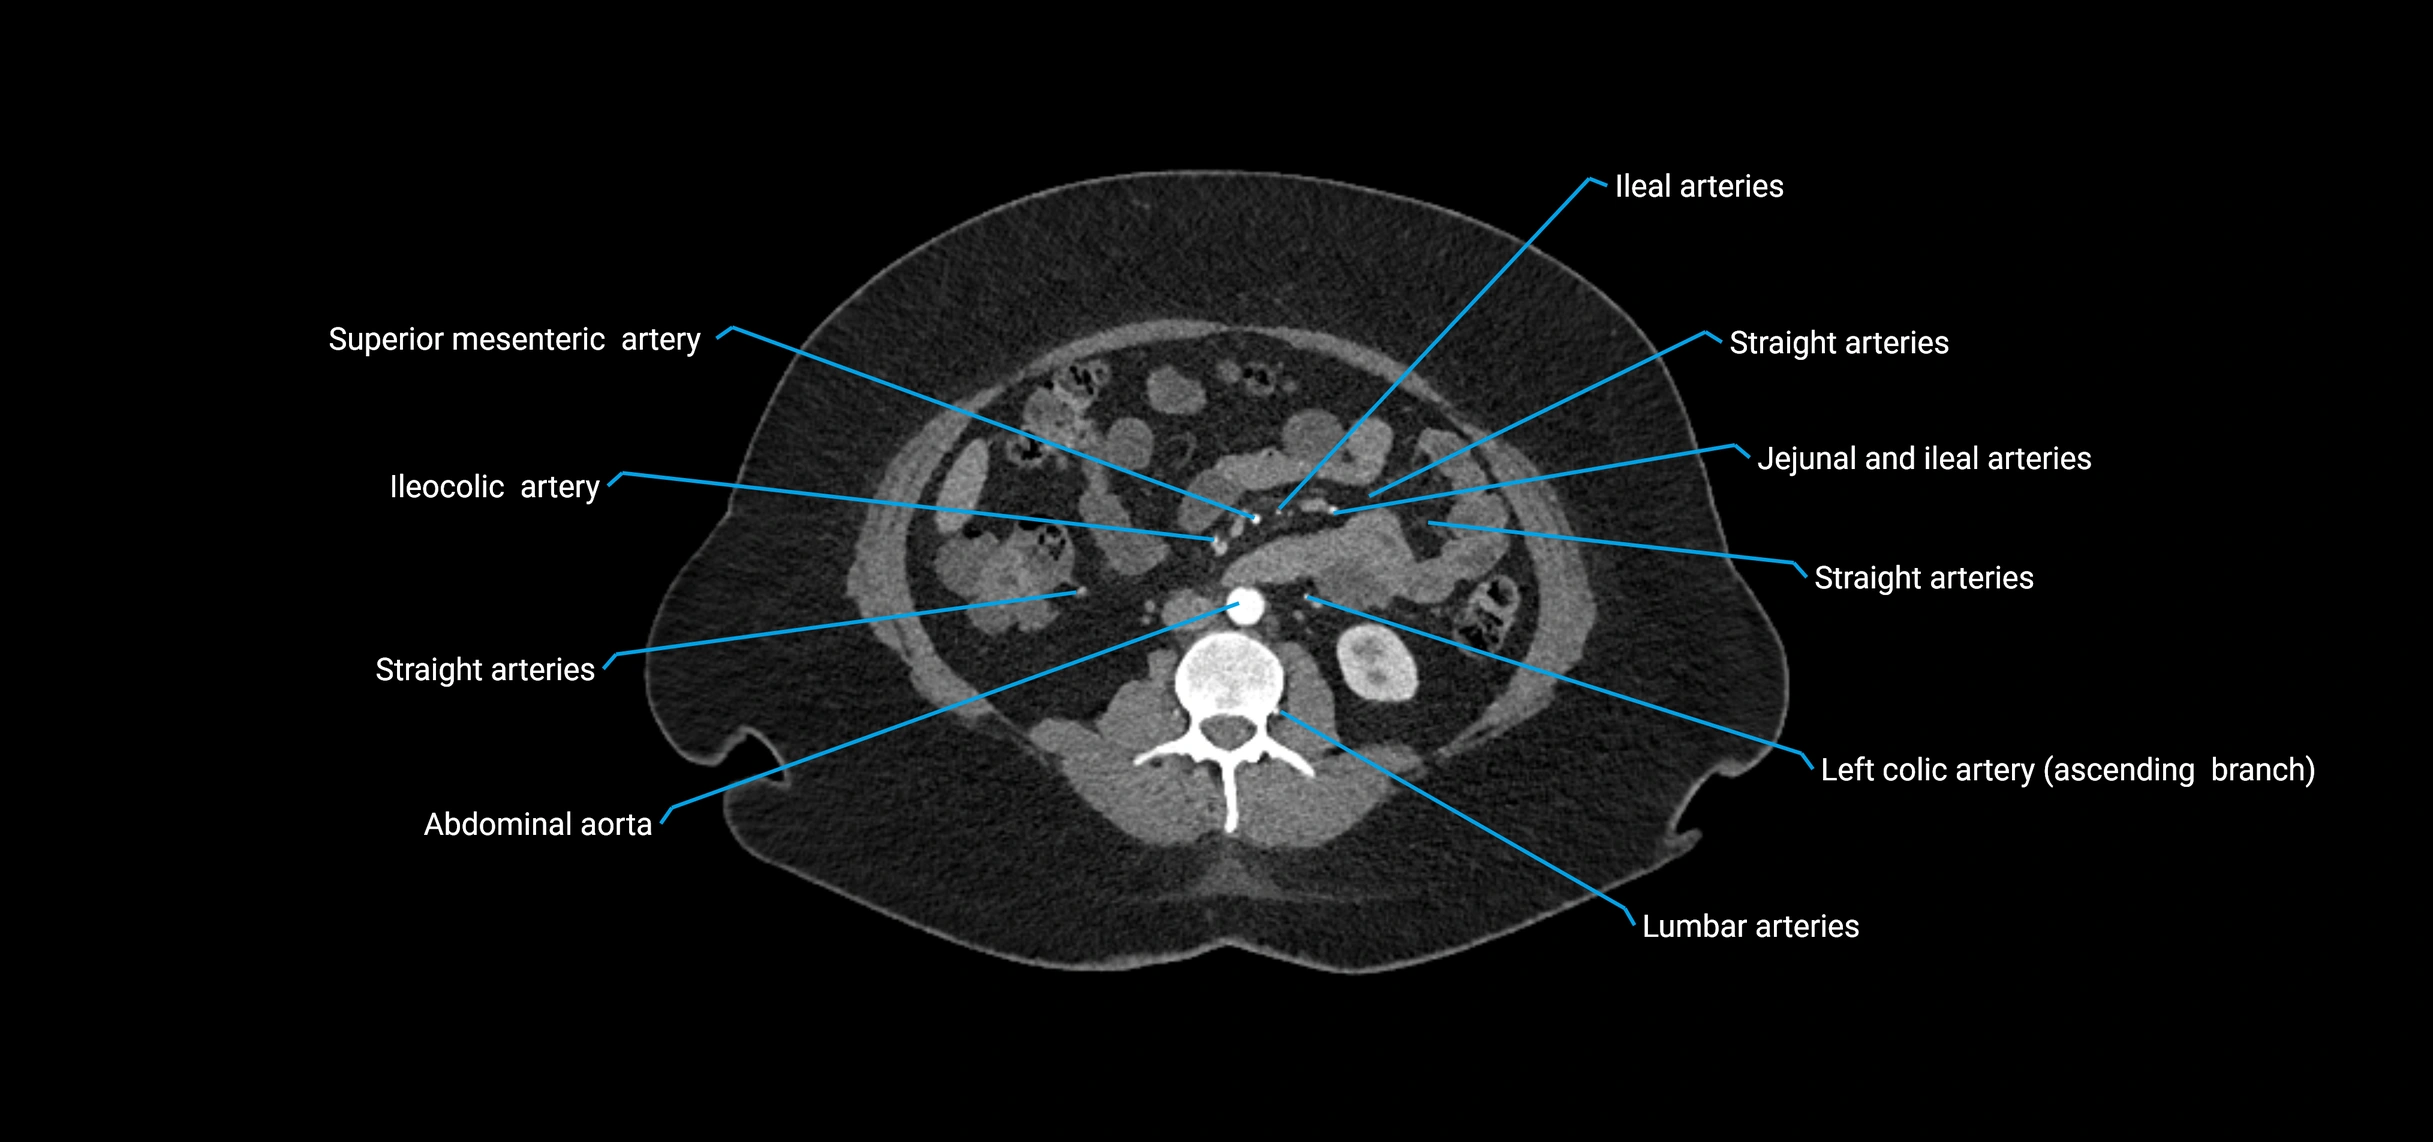

CT images

image

Contrast-enhanced CT (CTA):

• Gold standard for abdominal aortic imaging

• Provides excellent detail of lumen, wall, aneurysm, thrombus, and branch vessels

• Multiplanar and 3D reconstructions help in aneurysm measurement, stent graft planning, and dissection evaluation